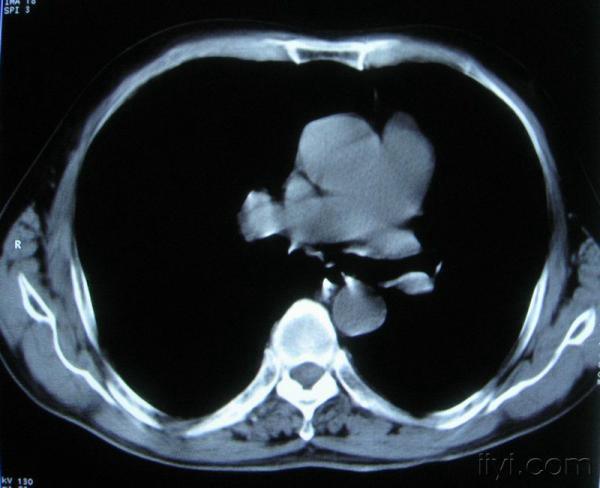

男。60岁,胸片示支气管炎治疗后复查CT。

你指那个肯定是淋巴结,中央系坏死,这很常见,特别在双侧腹股沟会经常看到。这个双侧腋窝及纵隔见多发小淋巴结征。

根据位置考虑应该是淋巴结,密度不均,是因为肿大的淋巴结中心液化坏死